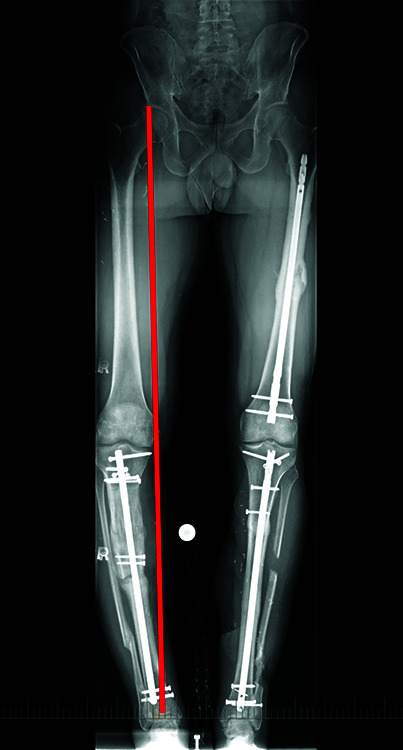

Case description: A 42-year-old male presented for complex right tibia reconstruction following a type IIIB open tibia fracture with a 92-mm bone defect. The bone defect was initially managed with an all-internal bone transport nail system (PRECICE bone transport). At the 13-month follow-up, the patient presented with a broken lengthening nail, varus limb deformity, and nonunion at the docking site. The nail components were extracted sequentially, and a burr hole was created in the distal segment of the nail through the nonunion site to facilitate removal. The residual varus deformity and tibial shaft nonunion were managed with a hexapod frame.

Conclusion: The IMLN was successfully removed without compromising limb reconstruction. By sequentially removing the components of the nail and altering the distal portion of the implant through the nonunion site, safe removal of the implant without further bone loss was achieved.